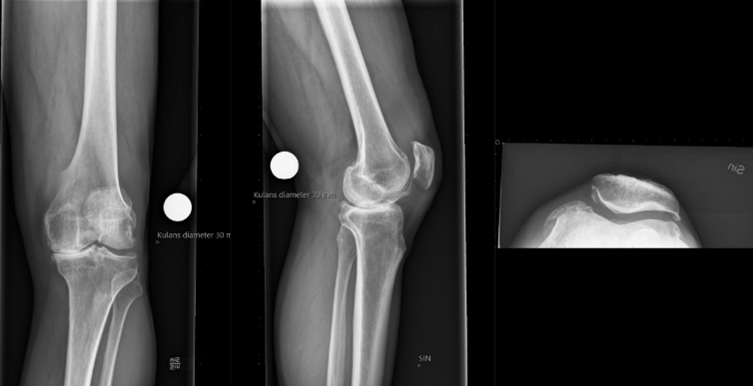

Röntgen inför proteskirurgi knä

• Viktigt i utredning för rätt vinkel av sågning osv. Kulan på bild är 30 mm

• Figursågning för att protesen ska passa perfekt. 6 grader valgus. Tibia rätvinkligt i frontalplan. Vi vill ha o-gradigt i HKA och efter som lårbenshalsen sticker ut lite snett vill vi ha lite valgus.

1. Korrekt benresektion enligt mallning/anatomi

2. Ligamentbalansering: dela strama strukturer så att ligamentbalansen blir korrekt både i flektion och i extension